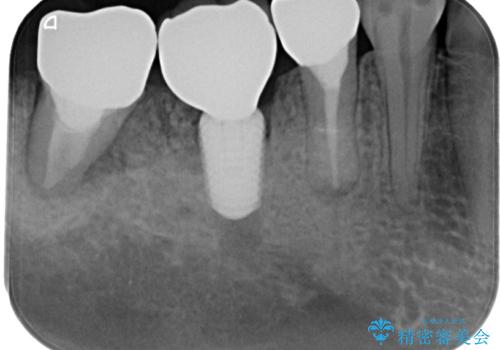

左下小臼歯は根管治療で対応する予定でしたが、診断のために歯肉を開いたところ頬側に垂直破折が認められたため、抜歯即時埋入インプラントによる補綴治療を選択することとしました。

右下は大臼歯部の歯は抜歯即時埋入インプラントにて、手前の歯は保存して補綴治療を行うこととしました。

インプラント埋入時に十分な安定値を得ることができたため、速やかに仮歯を装着し、最小限の通院回数で治療を終えることができました。